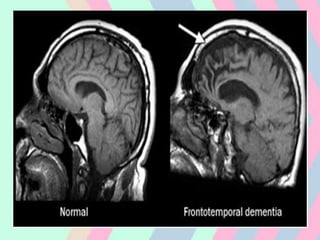

• Primary observation of structural and

functional brain imaging in neuropsychiatric

disorders such as dementia, movement

disorders, demyelinating disorders, and

epilepsy has contributed to a greater

understanding of the pathophysiology of

neurological and psychiatric illnesses and

helps practicing clinicians in difficult

diagnostic situations

• MRI in AD

• increased number of subcortical

hyperintensities, generalized atrophy(medial

temporal lobe) and ventricular enlargement

• Significant volume loss of up to 5 % brain

FUNCTIONAL MRI IN

DEMENTIA

• fMRI studies have consistently

demonstrated that patients with Alzheimer's

disease have decreased fMRI activation in

the hippocampus and related structures

within the medial temporal lobe during the

encoding of new memories compared to

cognitively intact older subjects.